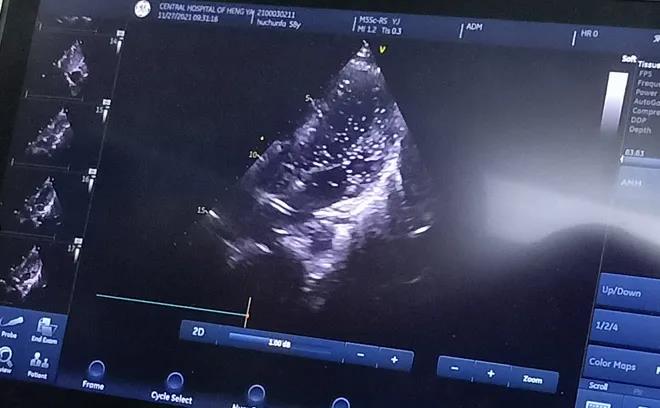

經充分的術前準備后, 11月27日上午,胡先生接受局部麻醉下經皮介入PFO封堵術,手術全程病人清醒,醫(yī)生一邊與胡先生交流,一邊進行手術,術后無傷口創(chuàng)面。患者當天即下床活動,復查心臟彩超提示封堵器位置良好。

胸超聲心動圖引導下經股靜脈房間隔缺損封堵術是在胸超聲心動圖實時監(jiān)測下的封堵術,與傳統(tǒng)開胸行房間隔缺損修補術相比,只需要通過大腿股靜脈進行穿刺便可完成,出血少、不縫針,真正做到了“微創(chuàng)”,創(chuàng)傷小且不影響美觀;與內科介入下手術相比,又避免了X線對患者的放射損傷。在胸超聲實時引導下操作,定位準確,隨時可調整封堵傘位置,適合于繼發(fā)孔房間隔缺損、室間隔缺損、動脈導管未閉等各種常見先天性心臟病的治療,對先心病心臟病患者的治療又提供了一項新的微創(chuàng)治療方法。該技術因創(chuàng)傷小、恢復快,術后3至5天即可出院。